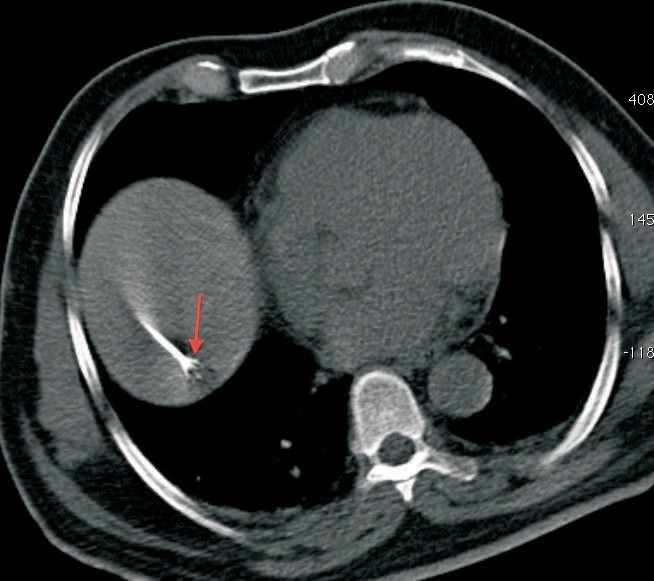

Recently we had an elderly gentleman with a solitary metastatic lesion (Fig. 1) measuring 1.2 cm in diameter in segment 7 of the liver, He had been operated earlier for carcinoma colon. We were able to safely introduce the RFA electrode into the lesion despite its deep location (Fig. 2), without puncturing the overlying pleura and lung, which were in the way. Since the lesion was close to the diaphragm, we had to take care to avoid puncturing the diaphragm. The lesion was ablated at 90 degrees for 7 ½ minutes and a good burn was achieved without any complications (Fig. 3).

RFA is indicated in liver metastases, typically as an alternative to surgical resection, either when resection is technically difficult, the patient is not a surgical candidate, or the patient has refused to undergo resection. If a good burn margin is achieved, the results are excellent.